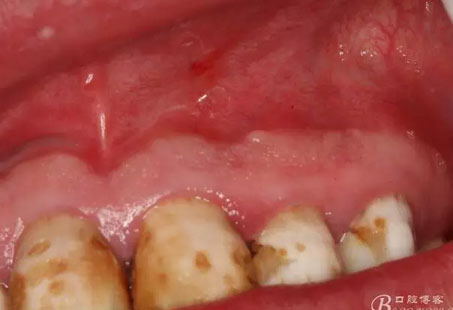

圖4.囊腫術(shù)前的口內(nèi)檢查:21、22牙冠未變色、唇側(cè)粘膜色澤正常,無(wú)瘺管,可在前庭溝捫及隆起,有乒乓感。